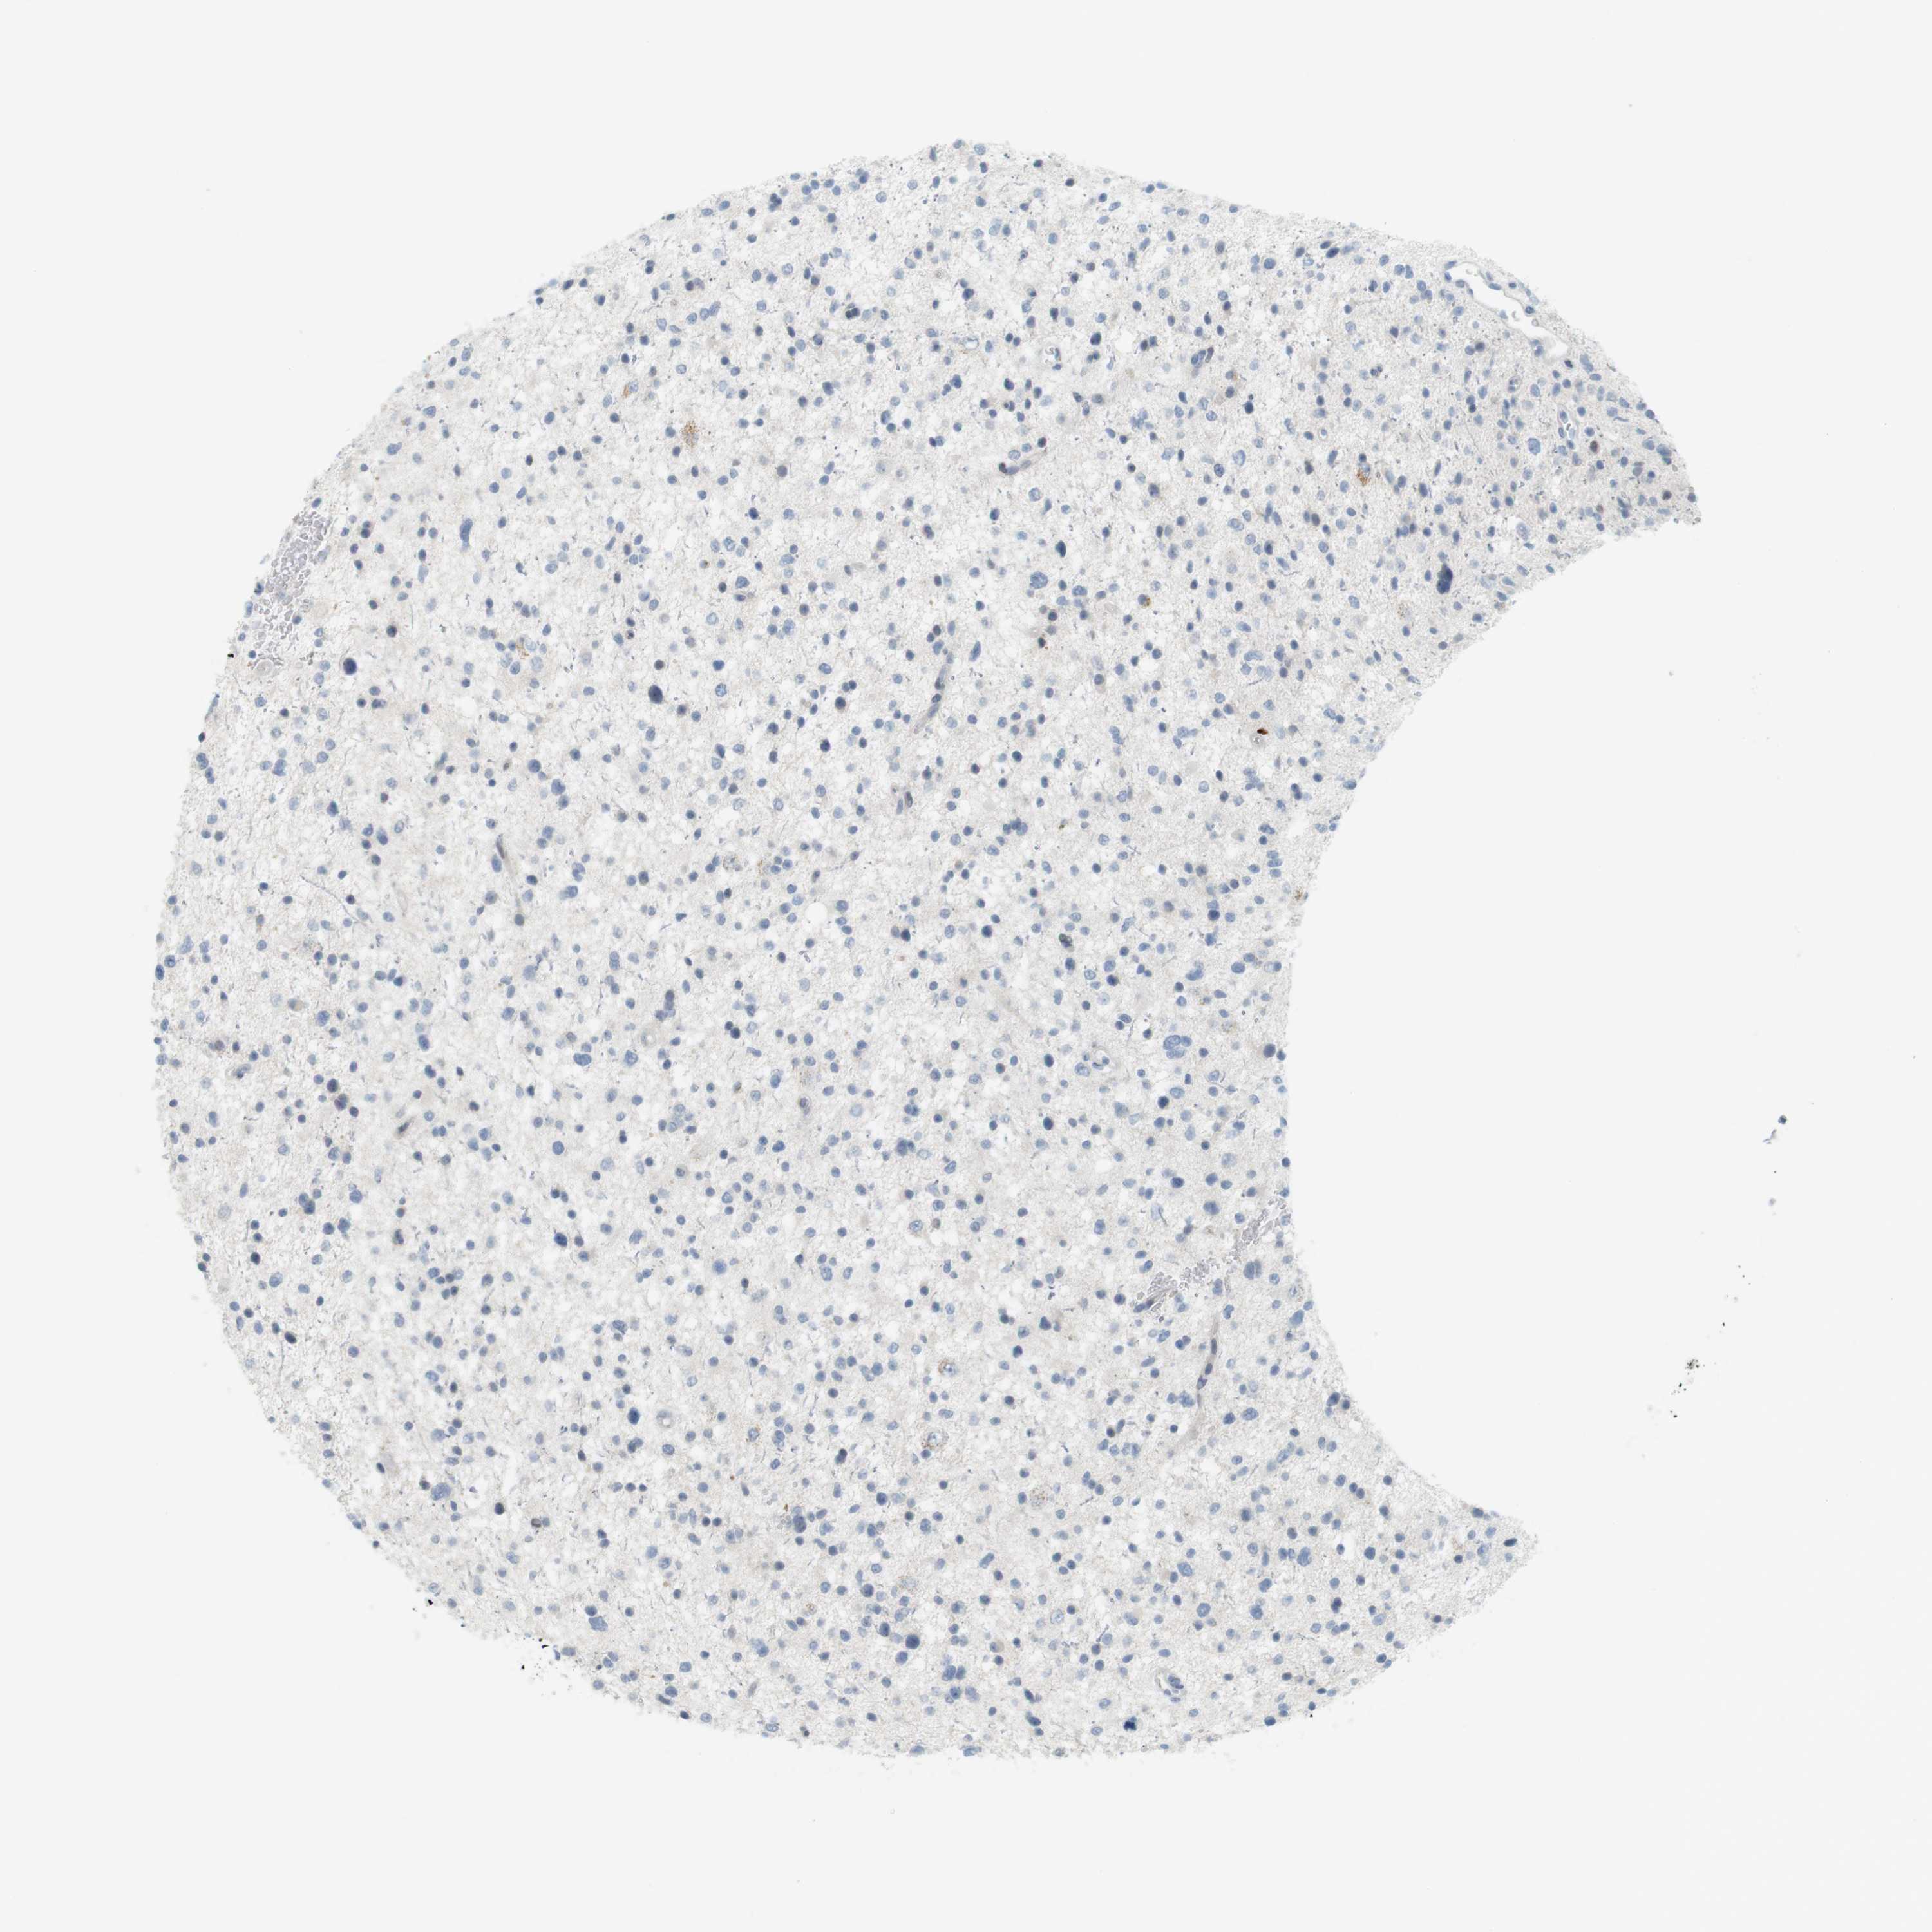

GLIOMA - Protein expressioni

A mouse-over function shows sample information and annotation data. Click on an image to view it in a full screen mode. Samples can be filtered based on level of antibody staining by selecting one or several of the following categories: high, medium, low and not detected. The assay and annotation is described here.

Note that samples used for immunohistochemistry by the Human Protein Atlas do not correspond to samples in the TCGA dataset.

Antibody stainingi

Antibody staining in the annotated cell types in the current human tissue is reported as not detected, low, medium, or high, based on conventional immunohistochemistry profiling in selected tissues. This score is based on the combination of the staining intensity and fraction of stained cells.

Each image is clickable and will lead to virtual microscopy that enables deeper exploration of all samples and also displays staining intensity scores, fraction scores and subcellular localization as well as patient and tissue information for each sample.

Antibody HPA001232

Antibody CAB015397

Staining

High

Medium

Low

Not detected

Intensity

Strong

Moderate

Weak

Negative

Quantity

>75%

75%-25%

<25%

None

Location

Nuclear

Cytoplasmic/membranous

Cytoplasmic/membranous,nuclear

Glioma, malignant, High grade

Glioma, malignant, Low grade